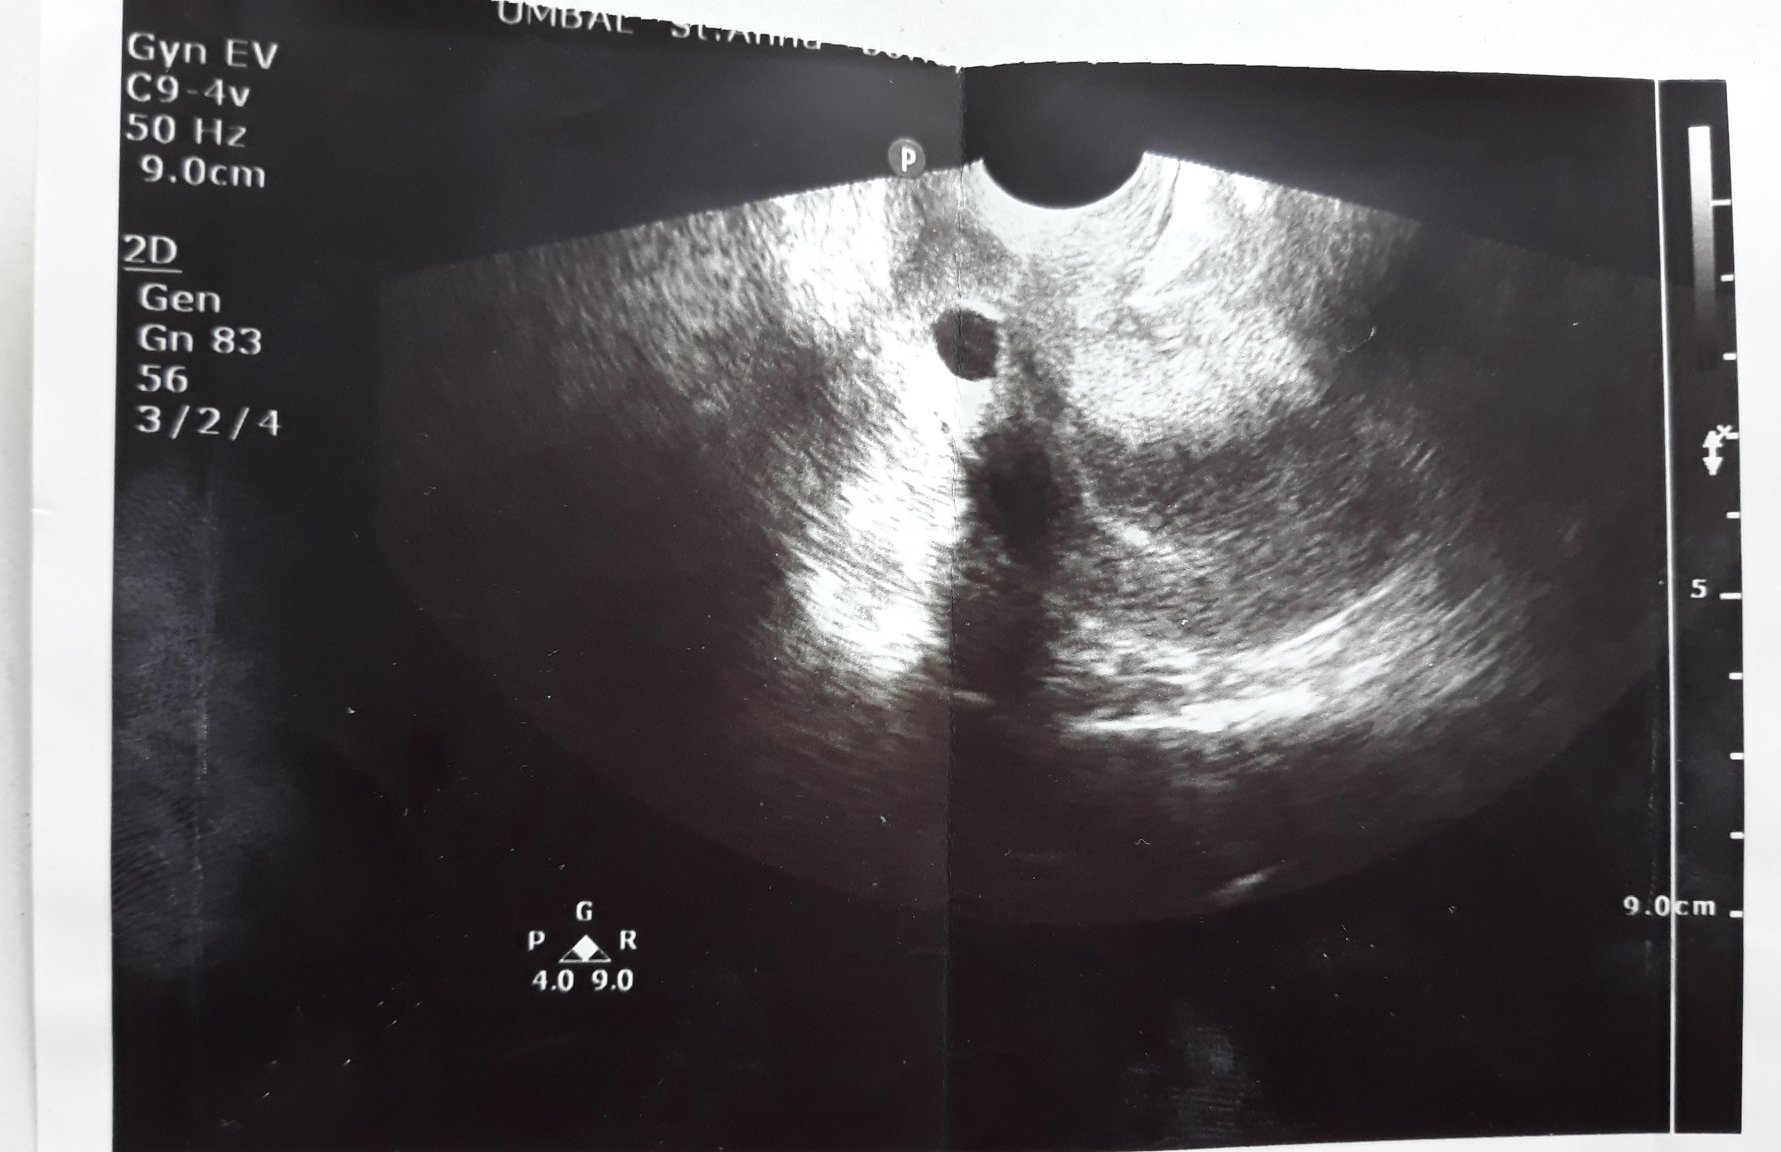

При ранните прегледи по време на бременност някои жени съобщават, че са видели само плодното сакче и не са чули сърдечен ритъм, което е нормално за този етап. Освен това има споделени случаи, когато лекарят е посочил нещо като мехурче, което също е често срещано в ранните етапи на бременността. Важно е да се отбележи, че сърдечните удари се откриват обикновено между 7-8 седмица.